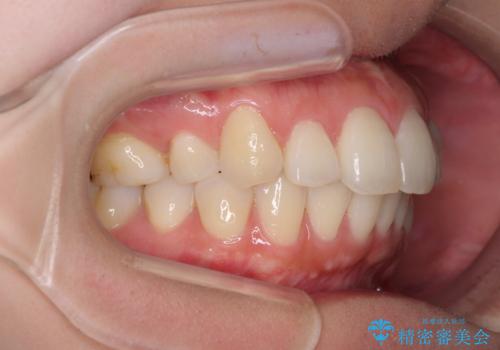

再矯正で突出した口元を引っ込める 抜歯矯正の後戻り

- 抜歯矯正の後戻りで前歯が突出してきていることを気にして来院された患者様です。

口元の突出感を改善するにあたり、抜歯矯正は行うことができないため、奥歯の後方移動とIPR(歯と歯の間を削る)により達成することとしました。

再度後戻りしたときに対応しやすいよう、インビザラインにて矯正治療を行うこととしました。

しっかりと装着時間を守り、ゴムかけにも協力していただいたので、口元を引っ込めることができました。